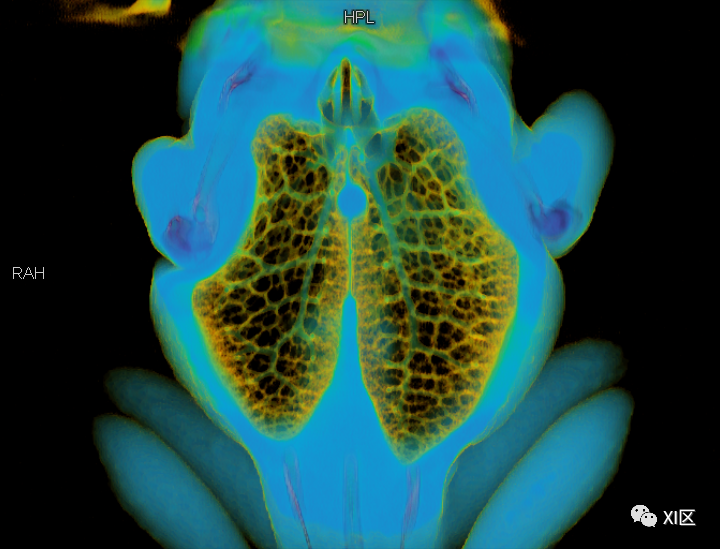

第二,

我们仔细观察了牛蛙的肺结构

不同于人类

牛蛙的两肺气管很粗大

直接和声门相连

气出来的更顺利

肺与气管、声门的位置关系

牛蛙肺部细节

肺部血管分布